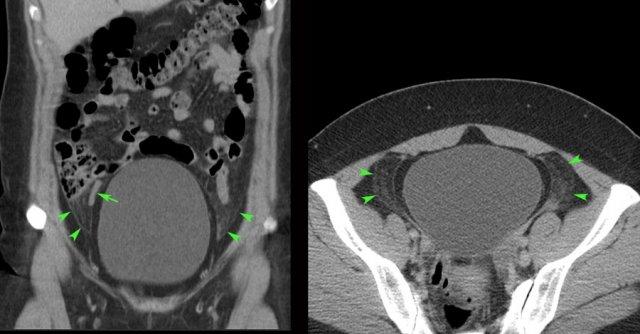

Bệnh nhân nữ 48 tuổi này nhập viện với các triệu chứng tương tự viêm ruột thừa và không biết mình đang mang thai.

Siêu âm cho thấy một khối lớn không đồng nhất, không có mạch máu (đầu mũi tên) ở phía phải và phía sau tử cung, nghi ngờ là cục máu đông lớn.

Ngoài ra còn có một ít máu đã hóa lỏng ở phía trên (*).

Xét nghiệm thai được thực hiện sau đó cho kết quả dương tính, và nội soi ổ bụng xác nhận thai vòi tử cung bị vỡ.

Ở bệnh nhân này được chuyển đến với nghi ngờ thủng dạ dày, một khối máu đông lớn không đồng nhất (đầu mũi tên) trong khoang phúc mạc trái đã được phát hiện (hình trên bên phải).

Một cục máu đông lớn như vậy có thể dễ dàng bị nhầm lẫn với mỡ mạc treo bình thường hoặc quai ruột.

Sự nhận thức và kiểm tra cẩn thận khối này, vốn không có nhu động, là những dấu hiệu hữu ích để phân biệt.

Bệnh nhân này cũng có nhiều dịch tự do, khi chọc hút xác nhận là máu đã hóa lỏng (hình dưới bên phải).

Nội soi ổ bụng phát hiện 1,5 lít máu và thai vòi tử cung bị vỡ.